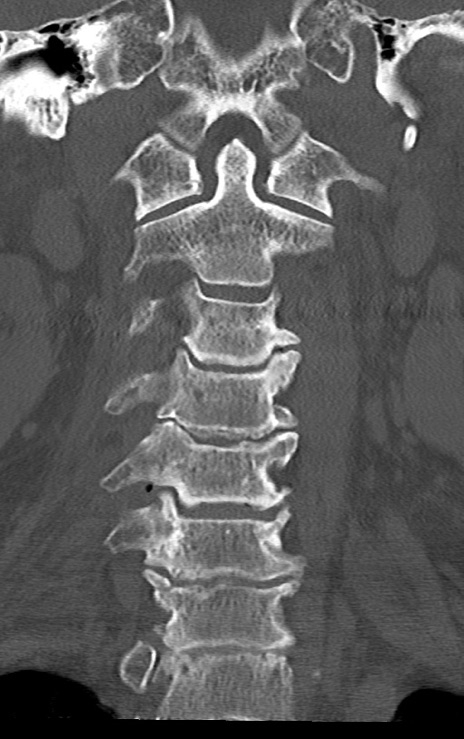

頚椎CT

矢状断像